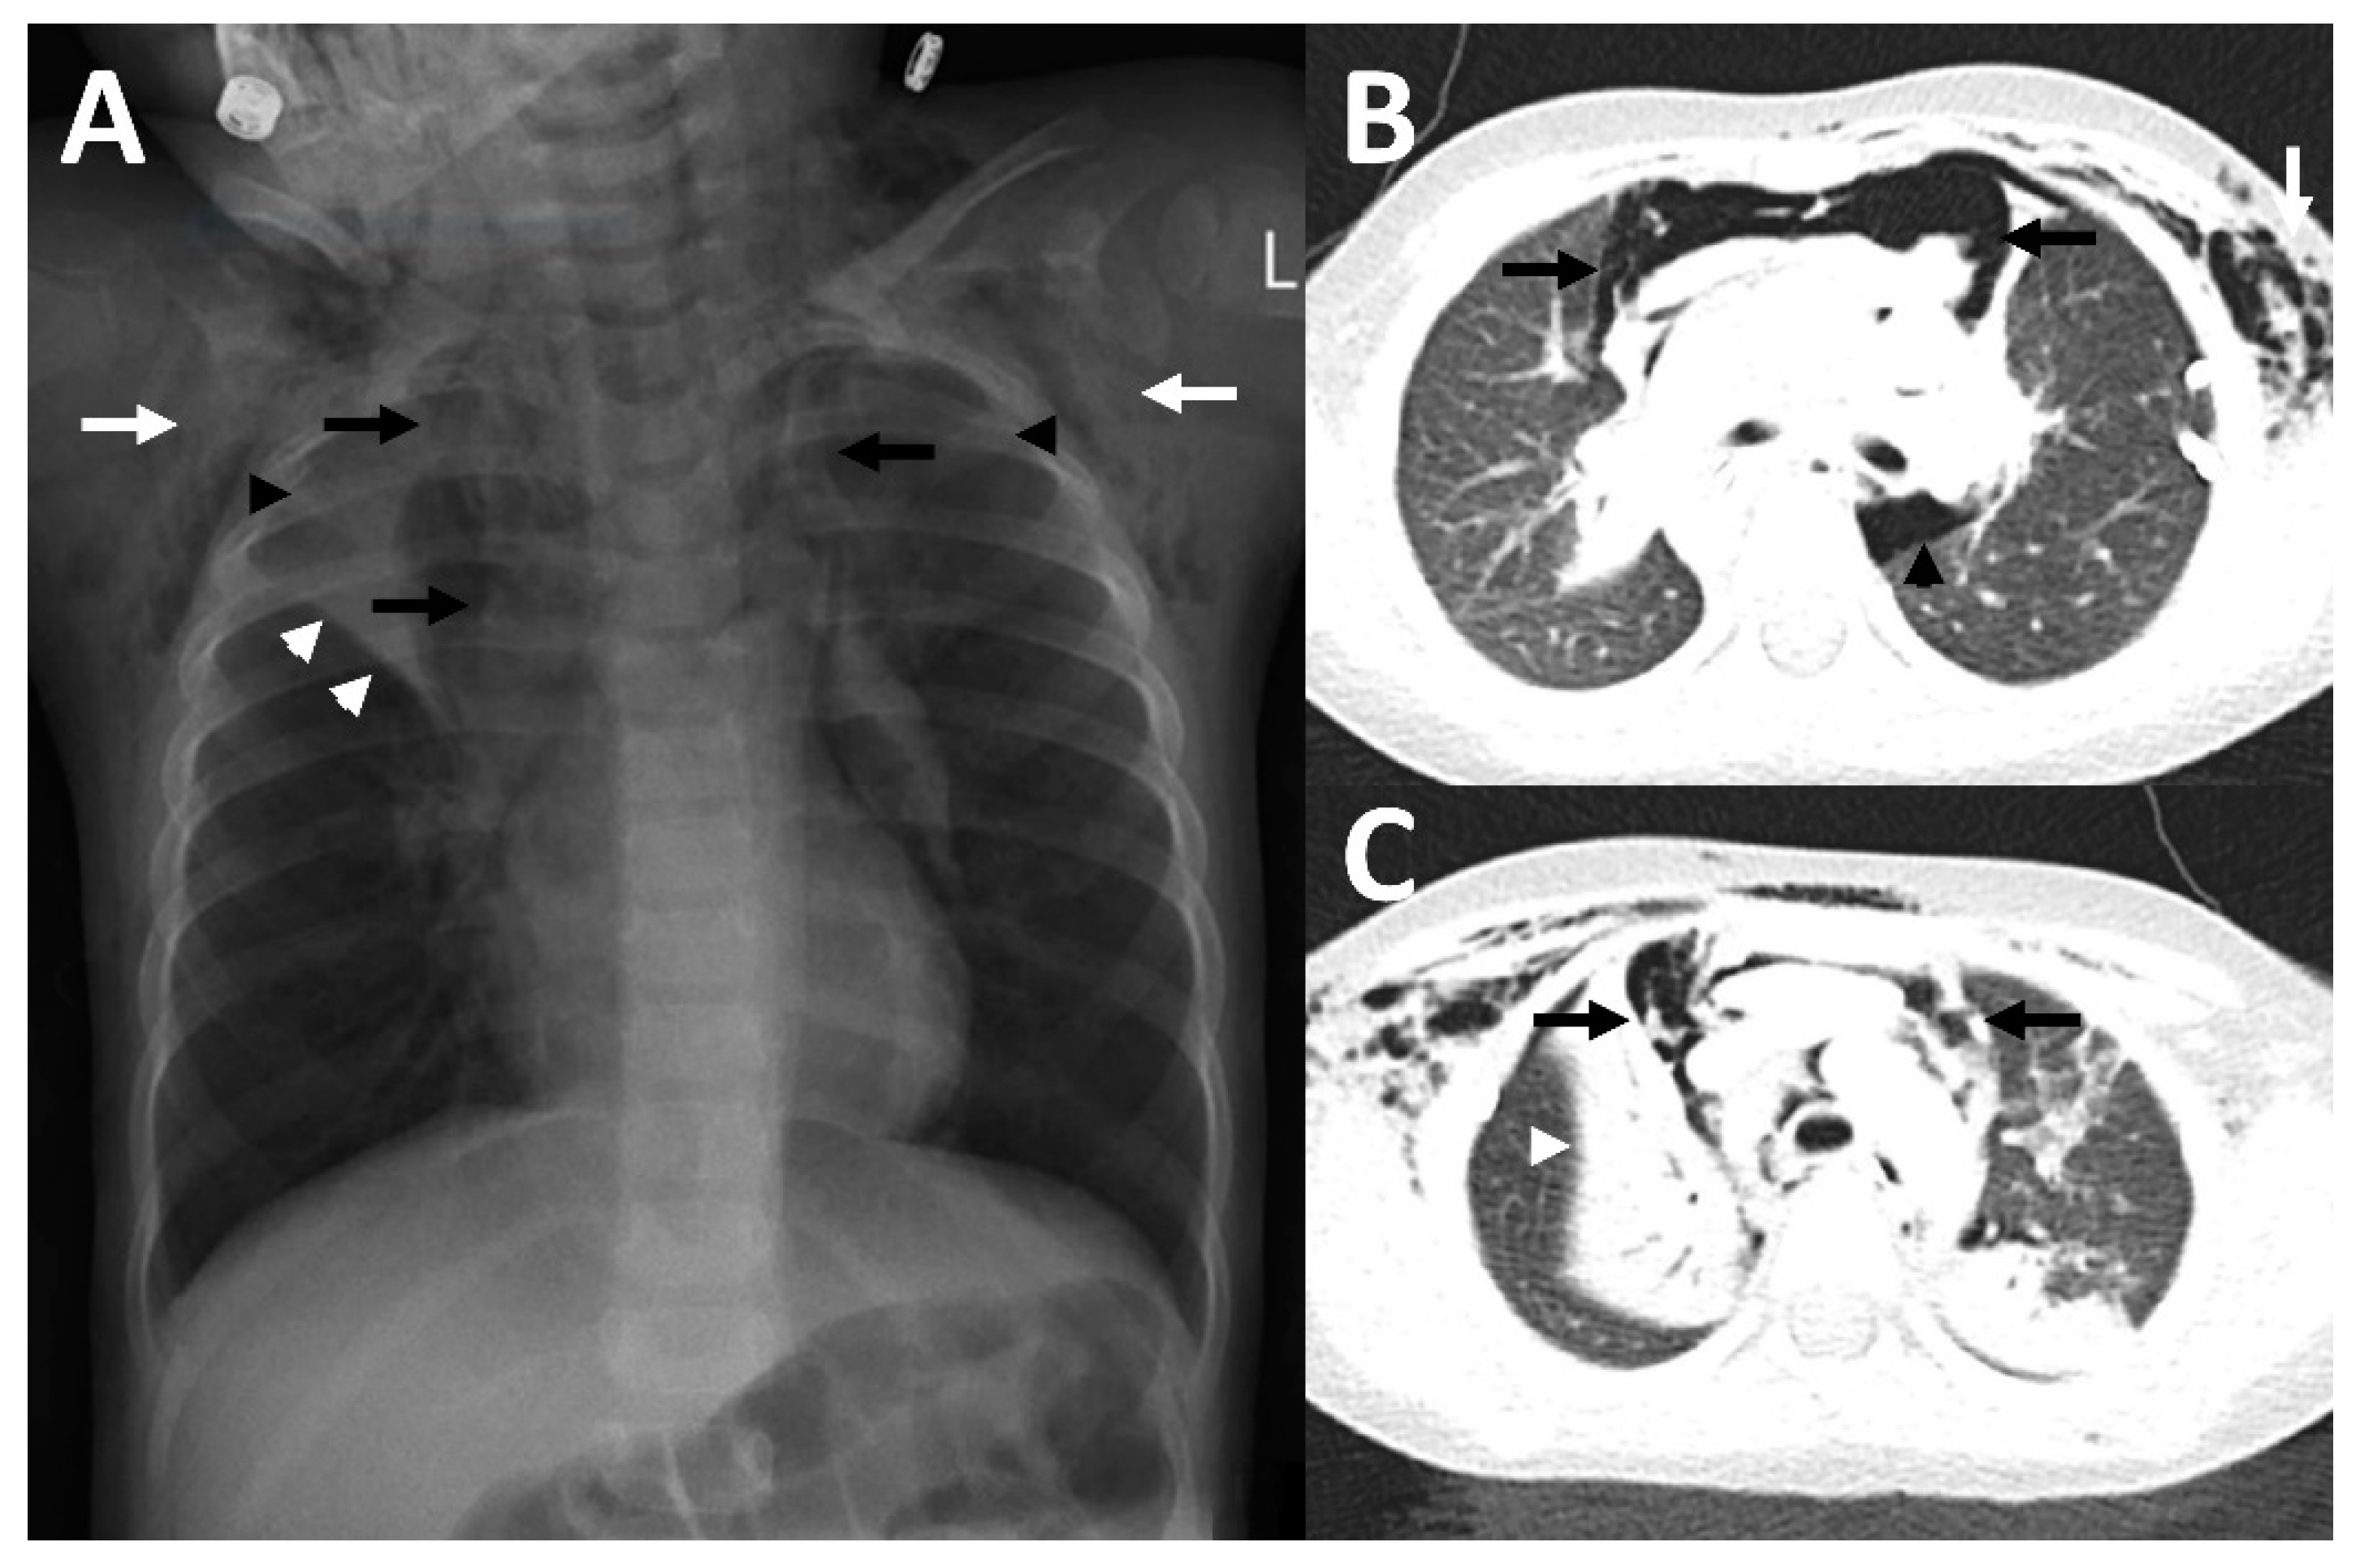

Figure 1.

Imaging findings in patient 1. Chest X-ray showing a pneumomediastinum (black arrows) and a subcutaneous emphysema, more pronounced on the left site (white arrows).